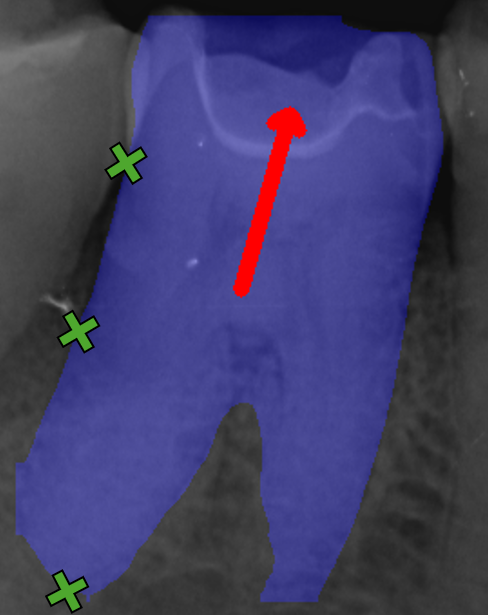

To evaluate the models’ ability to detect clinically relevant stages of periodontal disease, we employ metrics that compare classification performance for conditions necessary to diagnose periodontal disease stages. To compute these metrics, we derive the Percentage of Bone Loss (PBL) using the CEJ, BL, and RL keypoints on both the distal and mesial sides of each annotated tooth. The BL and RL locations are projected along a straight line extending from the CEJ, oriented according to either the predicted rotation index or the target bounding box angle, as seen in Figure 6. This gives us BL¯\overline{BL} and RL¯\overline{RL}, which are the projected bone level and root level, respectively. We then calculate the percentage of bone loss for a specified tooth side as PBL=CEJBL¯22CEJRL¯22\text{PBL}=\frac{||CEJ-\overline{BL}||^{2}_{2}}{||CEJ-\overline{RL}||^{2}_{2}}, where CEJBL¯22||CEJ-\overline{BL}||^{2}_{2} is the Euclidean distance of the CEJ keypoint and projected BL keypoint, and CEJRL¯22||CEJ-\overline{RL}||^{2}_{2} is the Euclidean distance of the CEJ keypoint and projected RL keypoint.

Refer to caption

(a) Keypoints

(b) Projection

Figure 6: Cropped image of Image104.png, with handmade example keypoints depicting the evaluation projection process. Keypoints are represented as green crosses, projected points as green dots, the rotation index as a red arrow and the projection from CEJ as red lines.